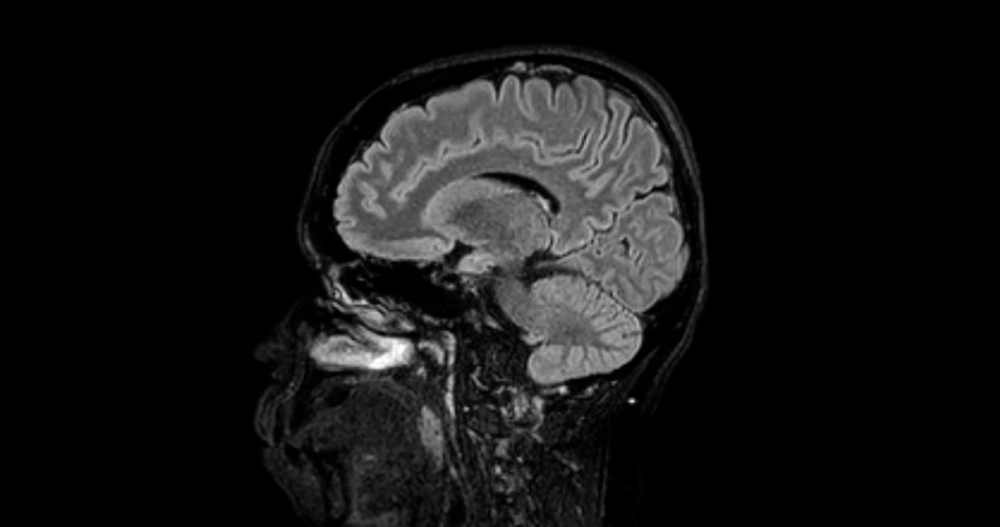

Pineoblastomos diagnozei patvirtinti gydytojas apžiūri pacientą, įvertina nusiskundimus bei ligos istoriją, taip pat atkreipia dėmesį į akių judesius. Tyrimų metu taikoma magnetinio rezonanso tomografija (MRT), kompiuterinė tomografija (KT), pozitrionų emisijos tomografija (PET). Taip pat gali būti būtina auglio biopsija – paimamas audinio mėginys iš naviko. Papildomai atliekami kraujo tyrimai ar smegenų skysčio analizė, norint įvertinti naviko žymes.